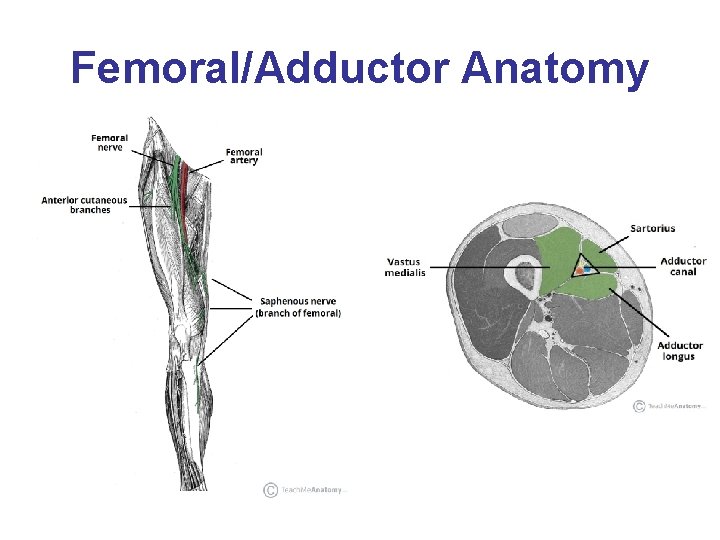

Femoral/Adductor Anatomy